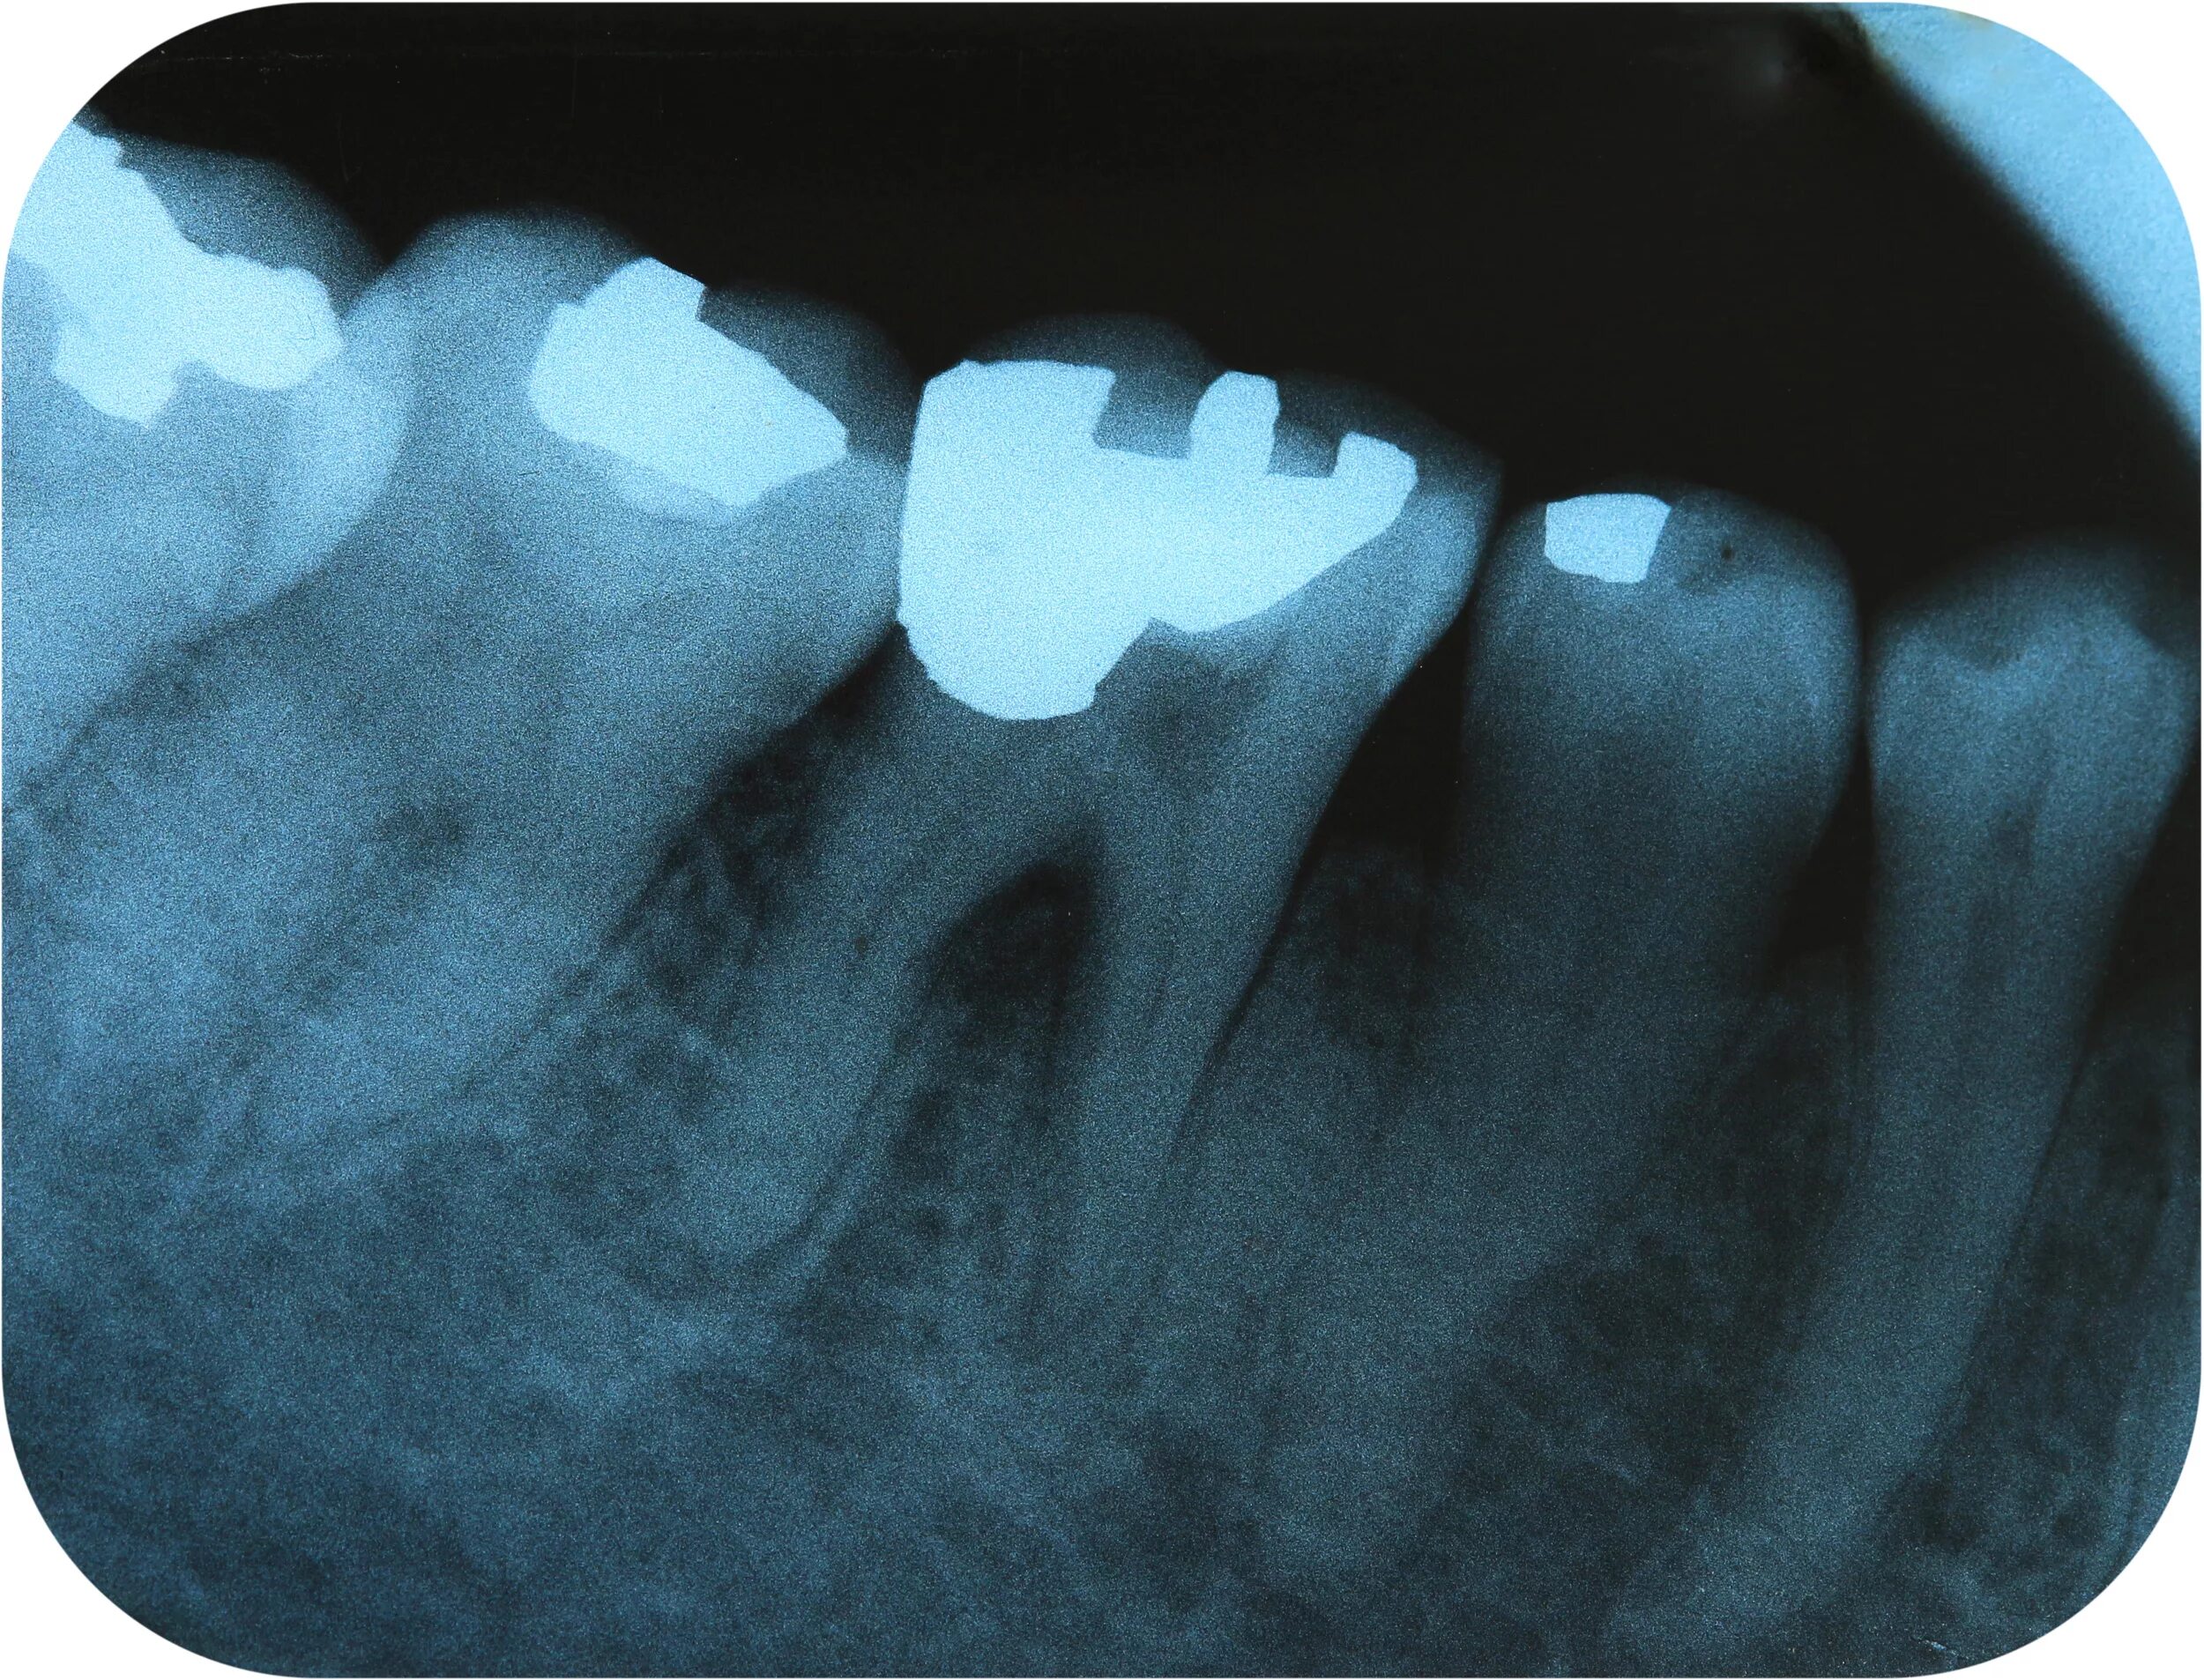

Входит в амальгаму